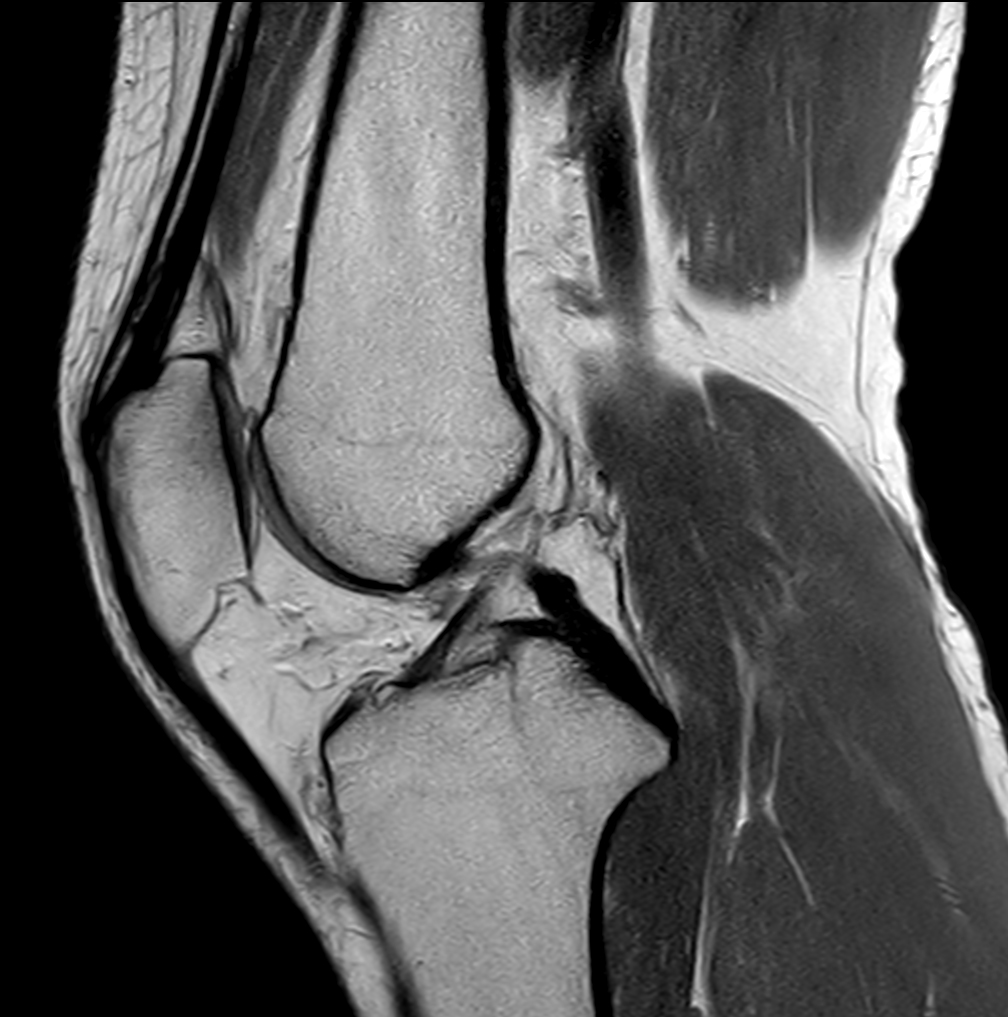

Coronal PDw TSE FatSat